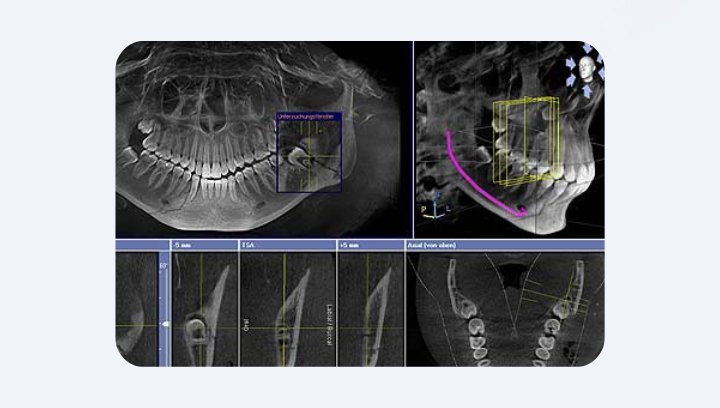

Удаление зубов мудрости

Зубы мудрости часто имеют сложное расположение: корни могут огибать нерв, упираться в соседний зуб или расти в пазуху. На панорамном снимке это выглядит как размытая тень — невозможно сказать, касается ли корень нерва или нет. КТ точно показывает пространственные взаимосвязи: в трёх плоскостях — горизонтальной, фронтальной и сагиттальной.

Если корень действительно прилегает к нерву, врач может выбрать иную тактику удаления. Это позволяет избежать потери чувствительности нижней губы или подбородка.

Главное отличие между моделями — в том, какую часть лица и челюстей аппарат видит за одно сканирование. Это называется FoV (Field of View) — поле обзора, то есть трёхмерный объём, который система формирует за один цикл.

Sirona AXEOS: FoV от Ø 5 × 5,5 см до Ø 17 × 13 см.

Этот аппарат может получить как изображение одного зуба, так и полный 3D-снимок обеих челюстей вместе с суставами, гайморовыми пазухами и носовыми структурами. Это идеальное решение для комплексной диагностики, ортогнатической хирургии, имплантации “full arch” и планирования цифровой эстетики.

Sirona Orthophos SL: FoV от Ø 5 × 5,5 см до Ø 11 × 10 см.

Этого объёма достаточно для подавляющего большинства клинических ситуаций — имплантации одного или нескольких зубов, диагностики гайморовых пазух, эндодонтического лечения или ортодонтического планирования.

Чтобы представить масштабы:

- 5 × 5,5 см — один зуб или сегмент из нескольких зубов.

- 8 × 8 см — одна челюсть.

- 11 × 10 см — обе челюсти с гайморовыми пазухами.

- 17 × 13 см — вся челюстно-лицевая зона: челюсти, суставы, синусы, носовая полость — всё за один проход.